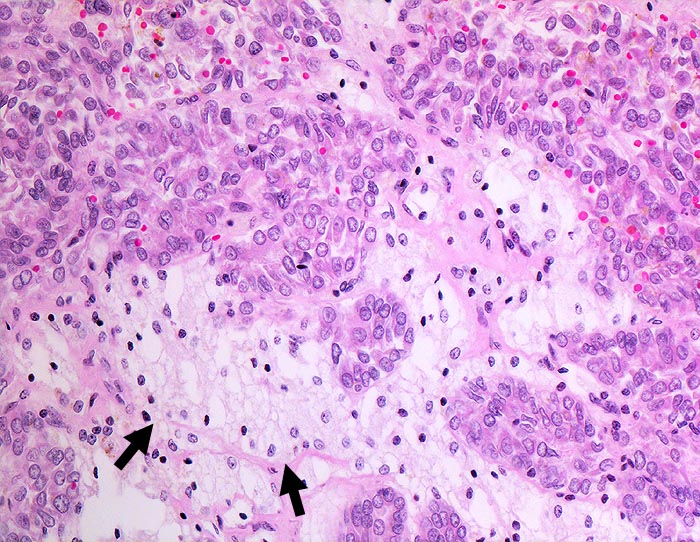

Maligner Pleuraerguss: Papilläres Nierenzellkarzin

Die papilliformen Verbände des papillären Nierenzellkarzinoms können mit pseudopapillären Verbänden reaktiver Mesothelien verwechselt werden. Die Positivität für BerEP-4 und die Negativität für den Mesothelmarker Calretinin bestätigen die Karzinomdiagnose.